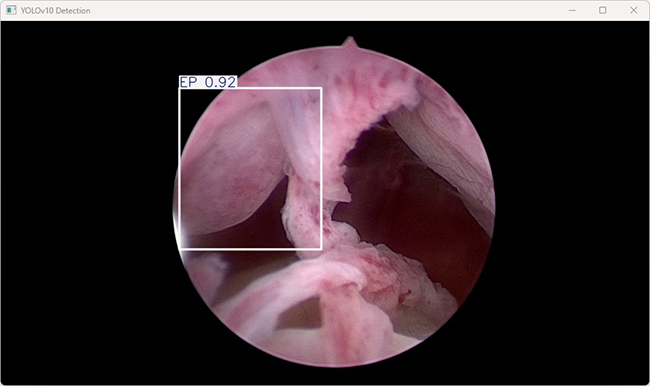

执行imgTest.py代码后,会将执行的结果直接标注在图片上,结果如下:

YOLOv10检测系统的推理结果日志。以下是对该结果的解析:

这段输出是基于YOLOv10模型对图片“imagetest.jpg”进行检测的结果,具体内容如下:

图像信息:

(1)处理的图像路径为:TestFiles/imagetest.jpg。

(2)图像尺寸为 384×640 像素。

检测结果:检测到 1 个目标类别为 EP “子宫内膜息肉”

处理速度:

(1)预处理时间: 2.3 毫秒

(2)推理时间: 45.5 毫秒

(3)后处理时间: 15.2毫秒

该检测任务运行成功,性能表现优秀,且能够准确检测出目标(EP)。